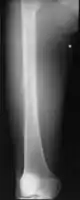

Medical imaging usually shows a well-defined wide-based bony growth on the surface of bone.[5] It can be pedunculated and irregular, giving it a "bizarre" appearance, and is not connected to underlying bone.[2]

MRI mid-upper arm

X-ray hand, BPOP 2nd metacarpal

X-ray hand, BPOP 2nd metacarpal (side view)